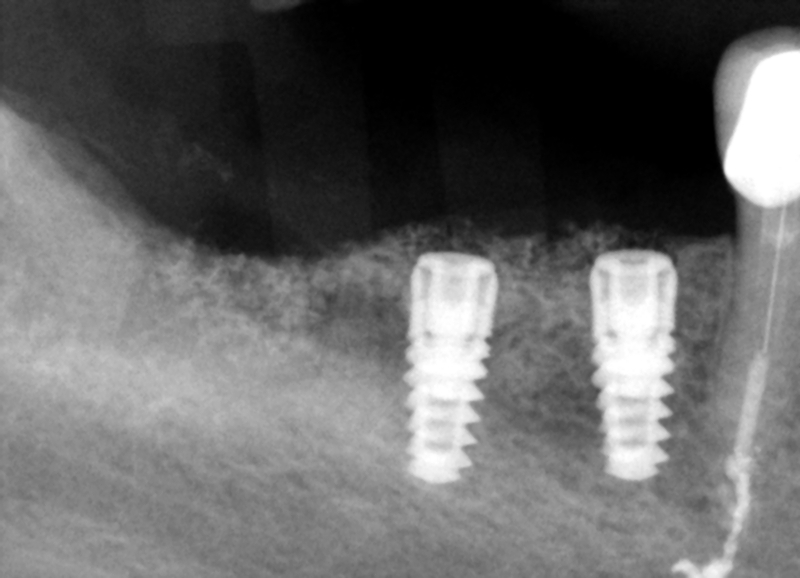

Three or four months later the graft is on its way to being replaced by the body's own bone and one can see the margins of the osteotomy have been bridged over. The increase in vertical height is evident.

Implants have been placed .